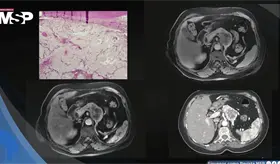

Lo que comenzó como un cuadro frecuente de dolor pélvico y dismenorrea en una mujer, terminó siendo un carcinoma folicular originado en estruma ovárico maligno. La paciente tenía solo 35 años, marcadores tumorales completamente normales y ninguna alteración tiroidea.